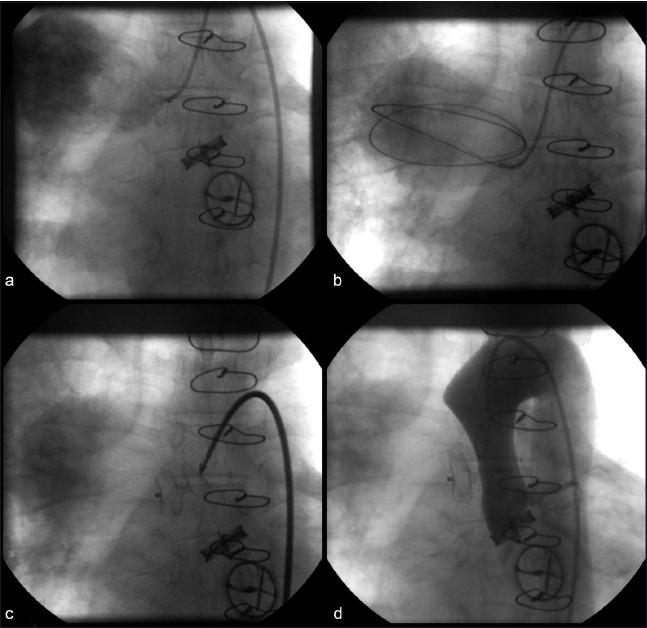

Pseudoaneurysm of ascending aorta is an infrequent but well-recognized and potentially fatal complication after cardiac surgeries. The complication can develop early, delayed or late, and the presentation is also varied. We are presenting here two cases of pseudoaneurysm of ascending aorta following cardiac surgery that were successfully managed by the transcatheter method. The first one occurred following coronary artery bypass surgery and the second one occurred following double-valve replacement surgery. The aortic openings of these aneurysms were occluded with 12 mm and 10 mm atrial septal occluders, respectively, with a good outcome. An immediate postprocedure angiogram showed no residual flow into the sac. Six months of follow-up of both cases also showed excellent results.

升主动脉假性动脉瘤是心脏手术后一种罕见但已被充分认识且可能致命的并发症。该并发症可早期、延迟或晚期发生,表现也各不相同。我们在此呈现两例心脏手术后升主动脉假性动脉瘤病例,均通过经导管方法成功治疗。第一例发生在冠状动脉旁路移植术后,第二例发生在双瓣膜置换术后。这些动脉瘤的主动脉开口分别用12毫米和10毫米的房间隔封堵器封堵,效果良好。术后即刻血管造影显示无血液残留进入瘤腔。两例患者术后6个月的随访结果也都非常理想。